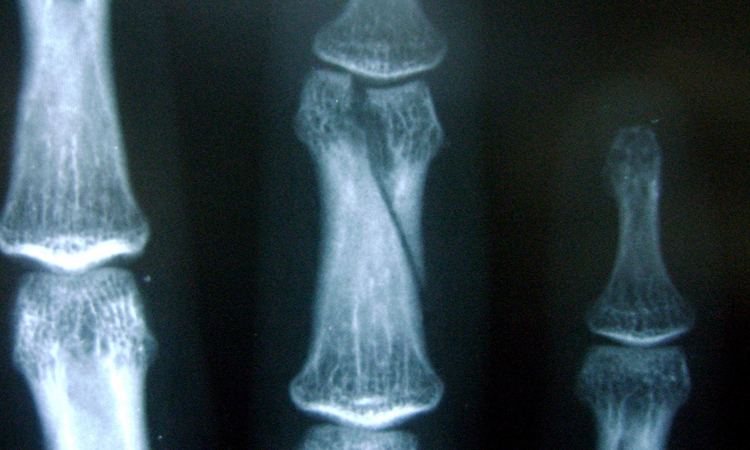

Los estudios de imagen que deben pedirse son radiografías simples de la mano, AP y oblicua, en donde se evaluará la localización exacta de la fractura, su configuración, el grado de desplazamiento, la angulación y la rotación del dedo.

Con la revisión del paciente y las radiografías el diagnóstico ya está hecho, y el tratamiento puede proponerse de acuerdo a la edad del paciente, la mano dominante, la actividad que realiza, el dedo afectado, si esta rotado o no, el tipo de fractura, el desplazamiento.